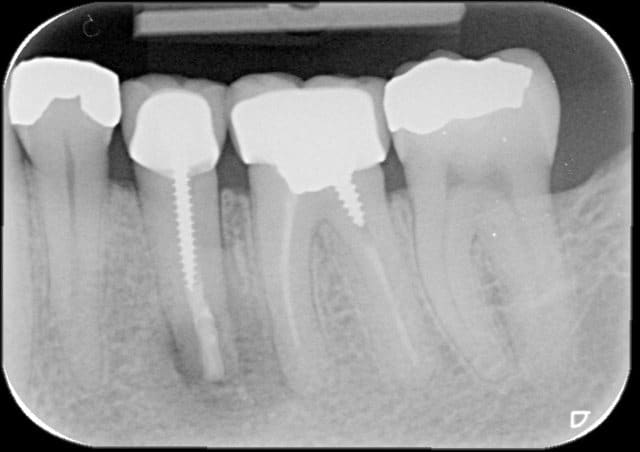

18/04/2013 à 14h30

Radio pre op avec mon endo a moi que j'avais faite qui a lamentablement echoué

l'endo avait l'air plutôt propre. bizarre.

> l'endo avait l'air plutôt propre. bizarre.

Oui c'est vrai et faite sous digue

- en ce qui concerne le cas je suis assez intrigué par la disparition du liseré de condensation osseuse à la marge de la lésion initiale, sur la radio post-op. Cela appelle une question de chronologie: la radio initiale est prise combien de temps après le traitement endodontique orthograde? et la post-op combien après la chirurgie?

Parce que vu d'ici, le réseau de trabéculations net dans la zone apicale fait penser à une rémission en cours confirmée par la disparition de la densification osseuse au pourtour de la lésion apicale sur la radio post-op. En d'autres termes je me demande s'il n'y a pas eu précipitation à ré-intervenir.

Je me faisais la même réflexion, mais matten a sans doute une image préop de l'endo initiale qui montre l'absence de lésion apicale!

La radio preop est un recadrage de panoramique effectuee 2 semaines avant la post op.